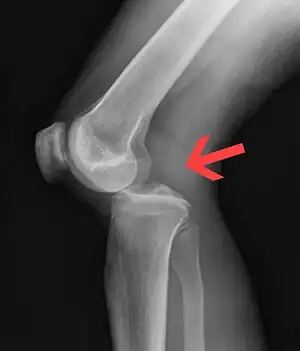

| Plain lateral X-ray of the left knee showing a posterior knee dislocation[1] | |

Plain X-rays, CT scan, ultrasonography, or MRI may help with the diagnosis.[2][9] Findings on X-ray that may be useful among those who have already reduced include a variable joint space, subluxation of the joint, or a Segond fracture.[5]